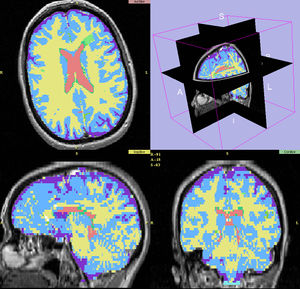

MRI-Only Based Radiotherapy Treatment Planning for the Rat Brain on a Small Animal Radiation Research Platform (SARRP)

Publication: PLoS One. 2015 Dec 3;10(12):e0143821. PMID: 26633302 | PDF Authors: Gutierrez S, Descamps B, Vanhove C. Institution: Medical Image and Signal Processing Group, Ghent University-iMinds Medical IT department, Ghent, Belgium. Background/Purpose: Computed tomography (CT) is the standard imaging modality in radiation therapy treatment planning (RTP). However, magnetic resonance (MR) imaging provides superior soft tissue contrast, increasing the precision of target volume selection. We present MR-only based RTP for a rat brain on a small animal radiation research platform (SARRP) using probabilistic voxel classification with multiple MR sequences. Six rat heads were imaged, each with one CT and five MR sequences. The MR sequences were: T1-weighted, T2-weighted, zero-echo time (ZTE), and two ultra-short echo time sequences with 20 μs (UTE1) and 2 ms (UTE2) echo times. CT data were manually segmented into air, soft tissue, and bone to obtain the RTP reference. Bias field corrected MR images were automatically segmented into the same tissue classes using a fuzzy c-means segmentation algorithm with multiple images as input. Similarities between segmented CT and automatic segmented MR (ASMR) images were evaluated using Dice coefficient. Three ASMR images with high similarity index were used for further RTP. Three beam arrangements were investigated. Dose distributions were compared by analysing dose volume histograms. The highest Dice coefficients were obtained for the ZTE-UTE2 combination and for the T1-UTE1-T2 combination when ZTE was unavailable. Both combinations, along with UTE1-UTE2, often used to generate ASMR images, were used for further RTP. Using 1 beam, MR based RTP underestimated the dose to be delivered to the target (range: 1.4%-7.6%). When more complex beam configurations were used, the calculated dose using the ZTE-UTE2 combination was the most accurate, with 0.7% deviation from CT, compared to 0.8% for T1-UTE1-T2 and 1.7% for UTE1-UTE2. The presented MR-only based workflow for RTP on a SARRP enables both accurate organ delineation and dose calculations using multiple MR sequences. This method can be useful in longitudinal studies where CT's cumulative radiation dose might contribute to the total dose. |

Illustration of a CB-CT and five MR images of the same animal. a) Coronal CB-CT image and (b)-(f) biased field corrected and masked coronal MR images using a T1-weighted (b), T2-weighted (c), ZTE (d), UTE1 (e) and UTE2 (f) sequence. All CB-CT images were first co-registered using 3D Slicer version 3.6.3 by rigid body transformations using normalized mutual information. |